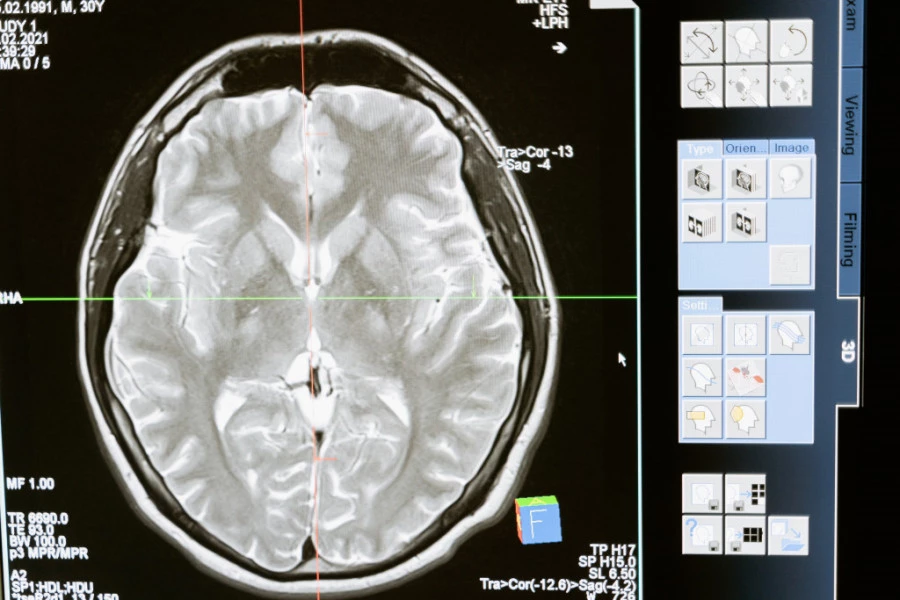

CT i MRI snimci otkrili su prisustvo cisti u mozgu, a dijagnoza je bila neurocisticerkoza, parazitska infekcija koja može nastati konzumiranjem zaraženog mesa. Lekari veruju da je parazit ušao u telo pacijenta nakon konzumiranja nedovoljno pečene slanine i putovao iz creva do mozga krvotokom, piše "Miror".

Na skeneru mozga su uočene promene